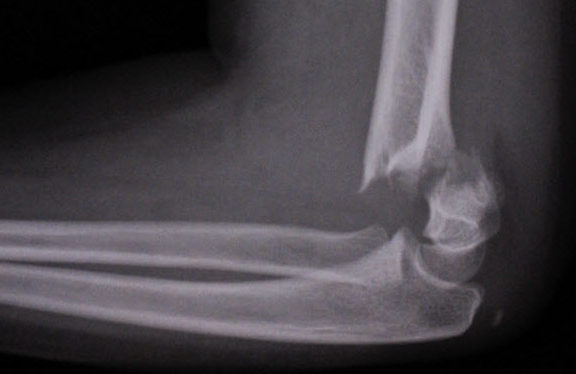

Supracondylar fracture

Displaced anterior fat pad (xray)